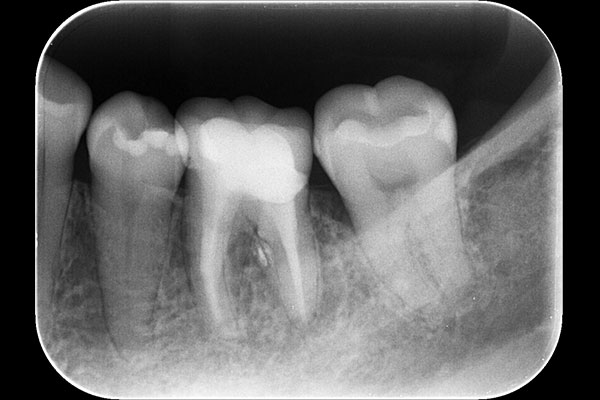

2.治療前のレントゲン

お口の中の診査と、レントゲンで一番後ろの歯が原因とわかり根の治療(感染根管治療)を開始します。

7.根管充填をした時のレントゲン

根管充填をした時のレントゲン写真です。

C型の根を詰めると、この様に帯状に詰め物が確認できます。